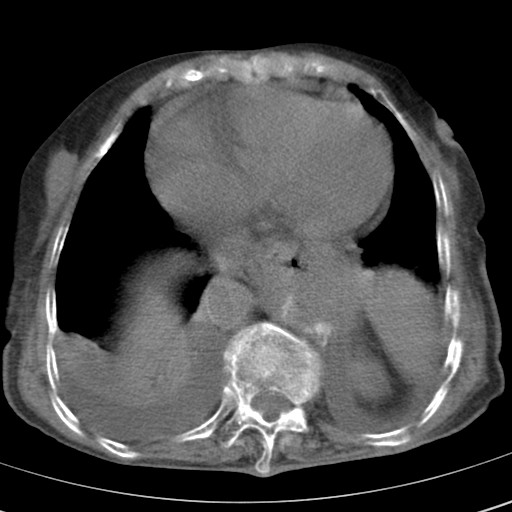

标题: CT21467:女,93岁,摔伤后检查。

女,93岁,摔伤后检查。

右肺炎症,心功能不全伴双侧胸腔积液,右下肺膨胀不全,食管裂孔疝,冠脉钙化,心包少量积液,左侧肋骨骨折,请上传骨窗.

食管裂孔疝

创伤性湿肺,双侧胸腔积液。可能有食管裂孔疝,进一步检查。骨折有无根据自己的机器及片子再仔细看吧。

右侧锁骨\\肩胛骨骨折、右侧湿肺,心功能不全伴双侧胸腔积液,右下肺膨胀不全,左膈破裂或食管裂孔疝,冠脉钙化,心包少量积液,请上传骨窗.

右肺炎症,心功能不全伴双侧胸腔积液,右下肺膨胀不全,食管裂孔疝,冠脉钙化,心包少量积液,左侧肋骨骨折,右肩甲骨粉碎性骨折。93岁,高寿哇!